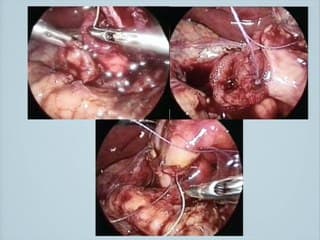

L'auteur chercheur à l'INSERM parle de l'HIFU qui est une technique d'utilisation d'ultrasons focalisée à haute fréquence dont le but est de produire des lésions. Expérimentation chez la guenon avec un monitorage échographique pour visualiser les lésions induites..Quel intérêt en pratique ? Par exemple pour le placenta accreta ou le TRAP !